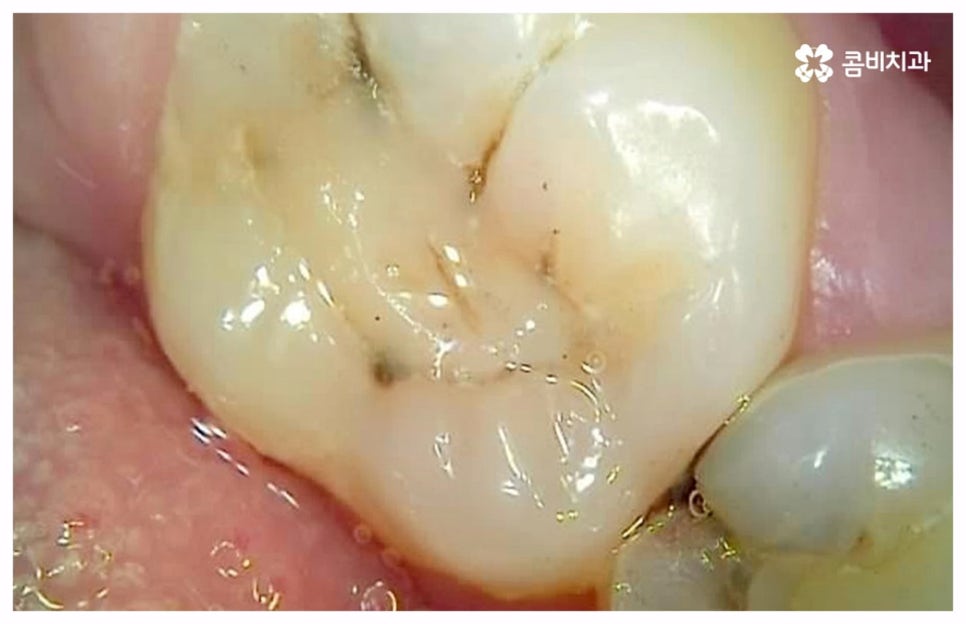

충치나 잇몸 질환은 보통 단계적으로 서서히 발전하기 때문에 환자분들께서 하루 아침에 극심한 통증을 느끼게 되는 경우는 많지 않지만 혹시라도 갑작스럽게 치통이 심할때 혹은 밤에 자려고 누웠는데 더욱 치통이 심할때 는 급성치수염을 의심해 볼 수 있어요. 급성치수염은 언급했던 충치나 외상성 치아 파절로 인해 치아 가장 안 쪽에 있는 치수 부분까지 세균이 침투하여 염증이 발생하는 것을 의미하는데, 이 때 감염된 혈관이 부어오르면서 단단한 치아 외벽에 둘러쌓인 치아 내부 압력이 올라가 작은 움직임에도 극심한 통증을 느끼게 되는 거예요.

특히 눕게 되면 머리 쪽으로 혈액이 몰리게 되면서 압력이 팽창하여 치통이 더욱 극심해지기 때문에 밤에 잠을 이루지 못할 정도로 고통스러운 경우가 많으며 상황에 따라 심각한 경우 발치까지 해야 할 수도 있기 때문에 될 수 있는대로 빠르게 치료를 받으실 필요가 있습니다. 보통 늦은 밤에는 치과 진료를 보지 않기 때문에 진통제를 복용하시는 분들이 많이 있는데 충치로 인한 통증에는 진통제가 효과가 있지만 급성치수염 같은 경우 진통제가 잘 듣지 않을 수도 있으니 너무 남용하지 않도록 주의하시길 당부드리고 있어요.

급성치수염에 대한 치료는 보통 안쪽까지 침투한 세균을 깨끗하게 긁어내고 염증 및 괴사된 치수 부분을 삭제한 다음 뿌리관(근관)을 소독하고 치과 충전물로 밀봉하는 신경 치료를 통해 이루어지는데, 이렇게 신경 치료를 진행하고 나서 후속 치료로서 남아있는 자연 치아를 보호하고 저작 기능을 제대로 수행할 수 있도록 하기 위해 주변 치아와 크기, 높이 등을 맞추어 딱 맞게 제작한 보철물을 덮어씌우는 크라운 치료를 해 주는 것이 자연 치아를 보다 오랜기간 동안 건강하게 사용할 수 있도록 하는데 크게 도움이 된다고 할 수 있어요. 경우에 따라서 앞니의 경우 신경관이 많지 않기 때문에 레진으로 치료를 마무리하는 경우도 있으니 참고해 주시면 좋을 것 같아요.